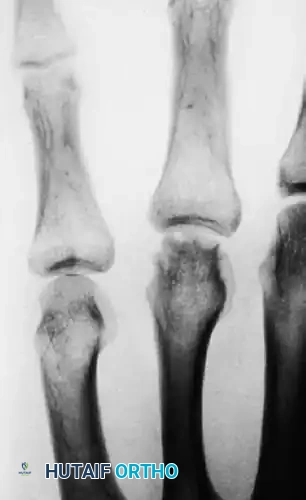

FIGURE 67-39 D: At 2.5 years, radiographs showed some biological remodeling, but definite incongruities of the metacarpal head persisted, predisposing the patient to early-onset post-traumatic osteoarthritis. (From McElfresh EC, Dobyns JH: Intra-articular metacarpal head fractures, J Hand Surg 8A:383, 1983.)